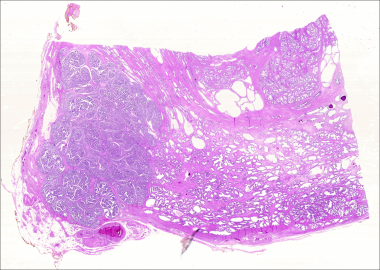

Breast tissue - pregnancy

The alveolar duct epithelium proliferates to form numerous secretory alveoli L, breast lobule; S, septa of interlobular tissue